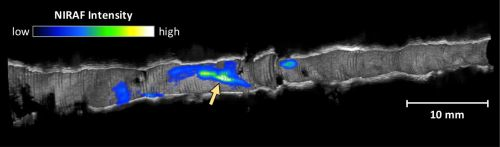

The primary results of the study were confirmation that the procedure was as safe and as feasible to perform as conventional OCT. The OCT-NIRAF images revealed that the NIRAF signal was elevated in areas in which OCT results suggested the presence of a fibroatheroma, and even higher in lesions with thin caps or at sites of plaque rupture and clot formation. Several aspects of the NIRAF signal were different from the patterns produced by other coronary vascular imaging modalities, and more investigation is needed to determine the molecular underpinnings and clinical significance of NIRAF signal results. NIRAF was also elevated in sites showing evidence of inflammation, another potential biomarker of plaques likely to rupture.